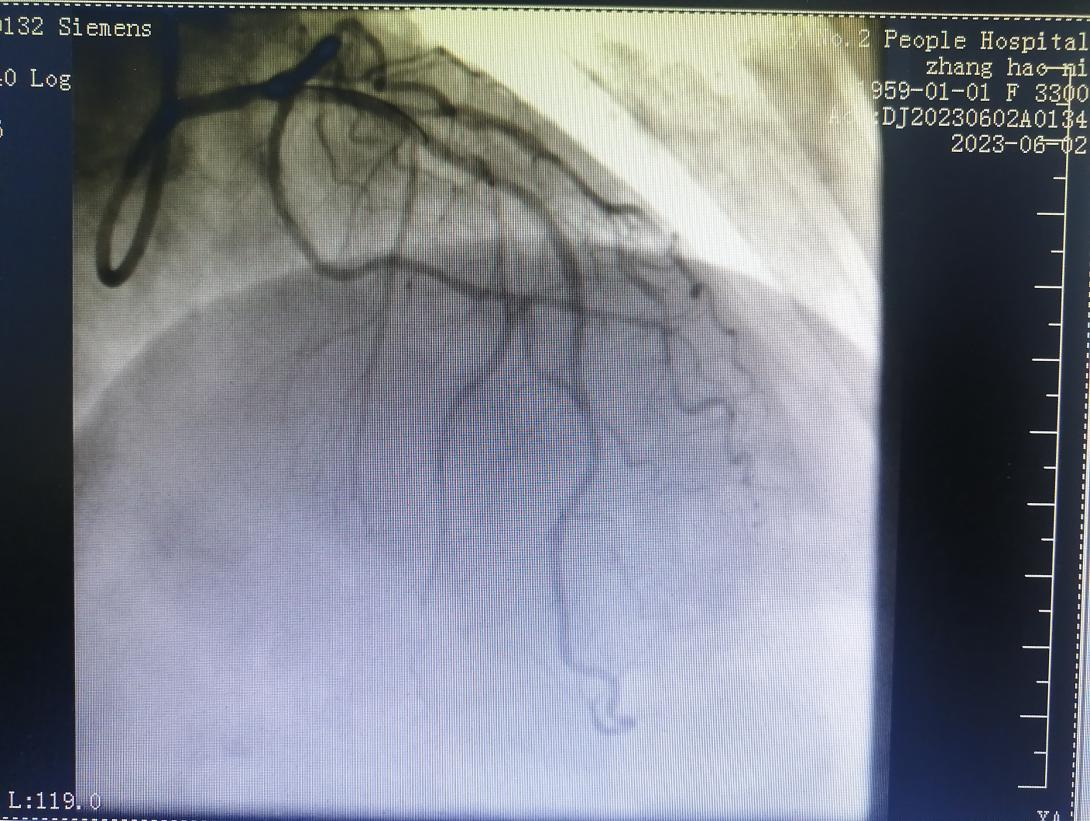

病例二

69歲的王阿姨,患有間斷性心前區(qū)不適2年。近日,因“心前區(qū)不適發(fā)作”入住心血管科。入院后,經(jīng)檢查冠脈造影發(fā)現(xiàn)前降支+回旋支閉塞病變。

金叔宣教授帶領(lǐng)心血管內(nèi)科介入團(tuán)隊(duì)為王阿姨制定了個(gè)體化的手術(shù)治療方案,即行右冠狀動脈造影+正向CTO,順利開通閉塞血管。

術(shù)后,王阿姨心前區(qū)不適癥狀較前明顯緩解。

術(shù)前: